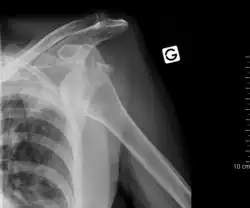

Raio-x anterior-posterior de uma luxação de ombro

A anamnese e o exame físico são fundamentais no diagnóstico. Especialmente os danos aos vasos sanguíneos e nervos devem ser observados e documentados.

Através de raio-x em diversos planos confirma-se o diagnóstico e uma fratura pode ser descartada. Pode ser solicitada uma ressonância magnética para ser descartada uma lesão Bankart.